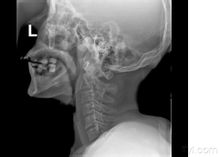

檢查方式

頸髓損傷X片臨床上通常可以通過X線顯示的頸椎骨折脫位的部位對頸髓損傷節段作出判斷,但有時頸椎的變化並不明顯,因此

需通過仔細檢查皮膚感覺障礙、肌肉運動障礙及反射的變化來確定。在解剖和功能的關係中,許多神經分布是交叉或重疊的,檢查時必須仔細加以辨認。有時甚至需經過反覆檢查,或從不同方向確定感覺障礙平面,才可獲得較準確的結論。頸3-4支配整個上頸部感覺,並表現為披肩狀分布的上胸部感覺。下位頸段損傷範圍需通過檢查上肢感覺分布來確定。